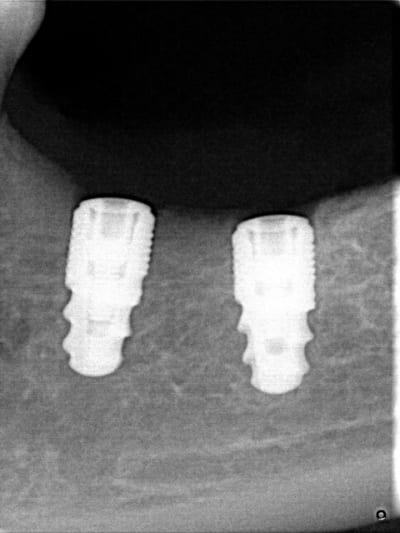

Merci pour vos réponses,au sujet de l'hypoesthésie ,je reçois ma patiente deux mois et demi après la pose des deux implants elle commence à sentir une sensibilité au niveau profond ,quel soulagement ,je prends une rvg et je découvre une réparation qui commence à se faire au niveau de la région qui a été lésée au moment de la pose !!!

je me permet de poster ses Rx qu'il m'a envoyé par émail